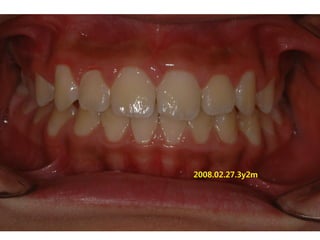

2008.02.27.3y2m

C.C

• Lower ant. crowding

Dx

• Deepbite, rhinitis, mentalis action

Goal

• Establish nose breathing and normal swallowing

pattern with T4K